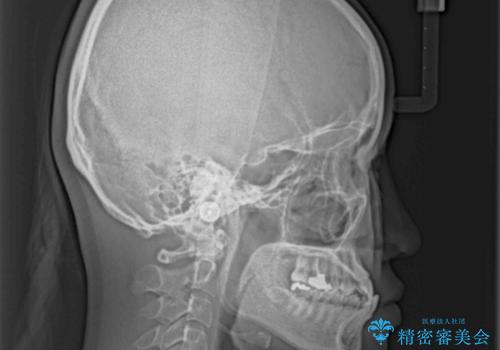

骨格的に下顎が前方に位置していましたが、歯列矯正で改善できると判断し、ワイヤー装置にて矯正治療を行うこととしました。